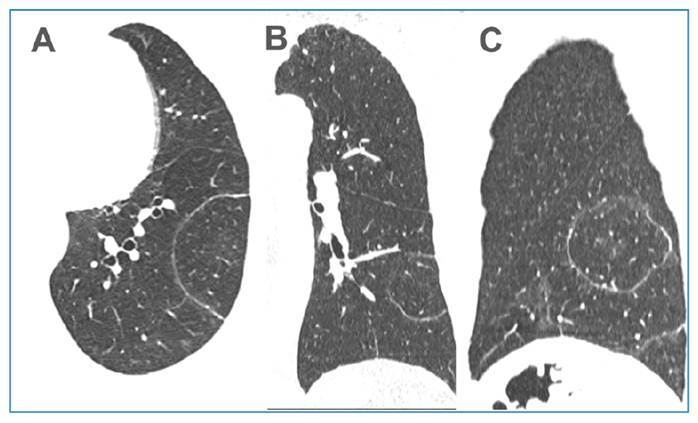

The CT target sign as a criterion for the differential diagnosis between tuberculosis and organizing pneumonia.

CT靶征作为结核与组织性肺炎鉴别诊断的标准。